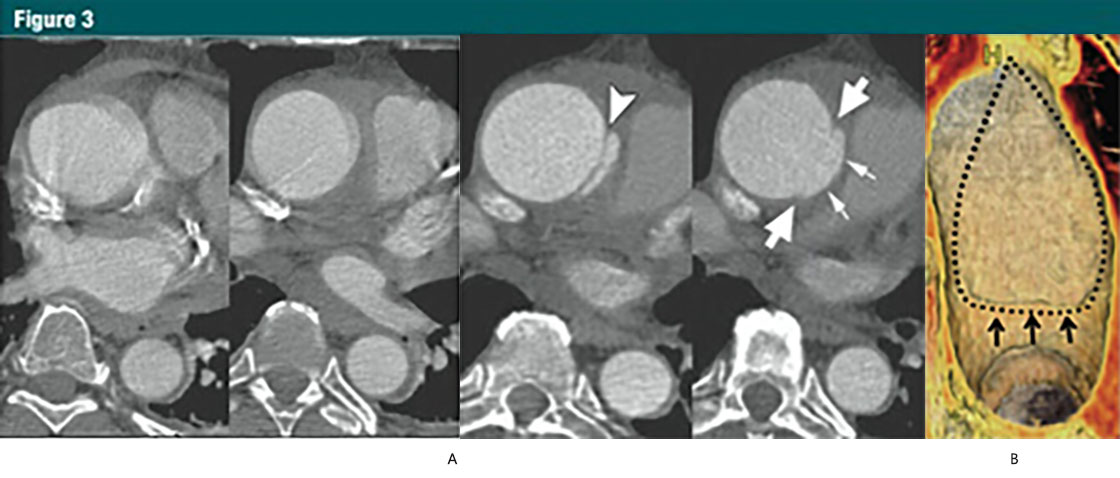

圖3 升主動脈局限性内膜撕裂

(A)上方:無心電(diàn)門控的CTA顯示升主動脈運動僞影,模糊;下(xià)方:12小(xiǎo)時後,心電(diàn)門控 CTA示:升主動脈近端内膜皮瓣(箭頭),伴随一(yī)個侵蝕邊緣的局限性内膜撕裂。局限性内膜撕裂的邊緣(大(dà)箭頭)和主動脈壁破壞形成的突起(小(xiǎo)箭頭)清晰可見。這些微妙細節如果沒有使用心電(diàn)門控是不可見的。

(B)VR重建顯示腔内一(yī)側6cm長的損傷。一(yī)個小(xiǎo)的破損皮瓣(細箭)代表撕裂的起始端,并一(yī)直延伸到主動脈弓的近端。虛線,代表撕裂的邊緣。(轉載,許可,引用24。)

少數有中(zhōng)層病變的患者,出現表淺或者部分(fēn)撕裂(相當于原發性内膜撕裂),但并沒有形成一(yī)個單獨的流出道,或者造成壁内血液的存留。這些少見的病變稱之為局限撕裂或者局限性夾層,與典型夾層對比往往具有細微的影像改變(30,33,36)(圖3)。

In a small number of patients with medial disease, a superficial/partial thickness tear develops (the equivalent of a primary intimal tear) without the development ofa separate flow channel or accumulation of intramural blood. These rare lesionsare referred to as limited tears or limited dissection and tend to have subtle imaging findings when compared with classic dissection (30,33,36)(Fig 3).